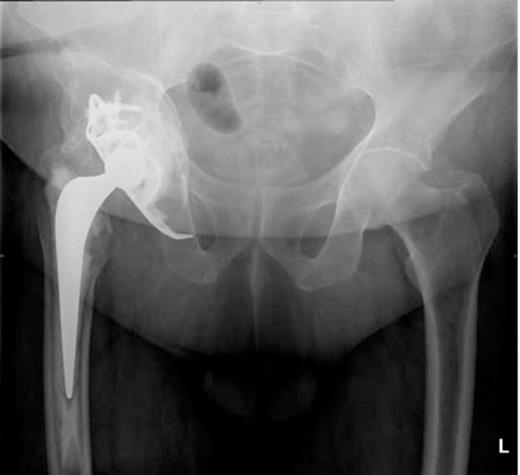

A post-operative radiograph (Figure 1) revealed medial migration of the acetabular construct prompting CT scans of his pelvis.

A pelvic radiograph showing migration of the acetabular construct

He was admitted to the High Dependency Unit for post operative recovery where he spent 6 days. On return to the elective ward, he made an uneventful recovery and required anticoagulation with warfarin for six months to protect the IVC filter. The most recent radiograph of his pelvis (Figure 4) showed excellent incorporation of the bone graft.

Regular out-patient reviews at 6 weeks, 3 months and 12 months reported satisfactory progress. Progression from crutches to independent mobilisation occurred during this time period.